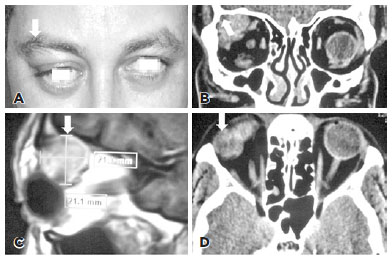

Though CT technique demonstrates an orbital isodense lesion in the superior lateral aspect of the orbit, magnetic resonance imaging (MRI) is a superior and a more valuable tool in the diagnosis of LGPA (Figure 2). Clarós et al. indicated that among the 52 cases they studied, MRI mostly showed lesions that were isointense to muscle on T1 (96.2%) and hyperintense to muscle on T2-weighted images(4,47) (94.2%). Further, only three cases (5.8%) showed infiltration of periorbital tissue(46).

05-fig02.jpg)

Diffusion-weighted (DW) MRI has also been described as a useful tool to differentiate benign from malignant lacrimal lesions(48,49). It is based on the molecular water motion of the tissue, which is changed by pathological processes. Apparent diffusion coefficient (ADC) calculated from the DW images can be used to differentiate these lesions. Benign lesions have higher ADC values, owing to their lower cellularity, than malignant lesions(4,48,49). Elkhamary found a mean ADC value of 1.21 ± 0.03 · 10−3 mm2/s for LGPAs, while the mean ADC value for malignant lacrimal gland lesions was 0.76 ± 0.14 · 10−3 mm2/s(48). Conversely, Ahmed et al. found an ADC value of 1.8 · 10−3 mm2/s for LGPA and 1.2 · 10−3 mm2/s for malignant lacrimal gland tumors(49). Elkhamary established a cut-off level of 0.90 · 10−3 mm2/s to differentiate benign from malignant lesions, with an accuracy of 90% and an area under the curve of 0.95(48), while Ahmed et al. established the cut-off value at 1.25 · 10−3 mm2/s(49). Further radiological investigations suggested malignancy, including invasion of the bone cortex(1,13,48), ill-defined tumor extension outside of the lacrimal gland, and molding around the globe(12). Watanabe et al. identified several cases of LGPA depicting rim calcification although this imaging feature was not reported by others(12). The primary clinical findings of LGPA are summarized in table 2.

Several factors, including incomplete resection during the first surgery, intraoperative spillage of tumor cells, or the natural history of the tumor could be attributed to a risk of relapse(1,3,6,13,19,22,27,45). The literature adequately suggests that biopsy is not necessary if appropriate imaging studies are conducted(20,38,46). With this background, MRI is the preferred method for examination of intracranial infiltration(20,38,46). According to Clarós et al., in LGPA the MRI shows lesions isointense to muscle on T1 and hyperintense lesions on T2-weighted images(4,6,46,47).